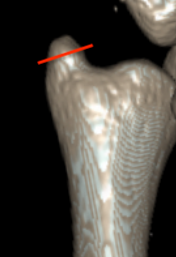

Classification ulna styloid fractures

| Type 1: Tip | Type 2: Base | Type 3: Proximal to styloid |